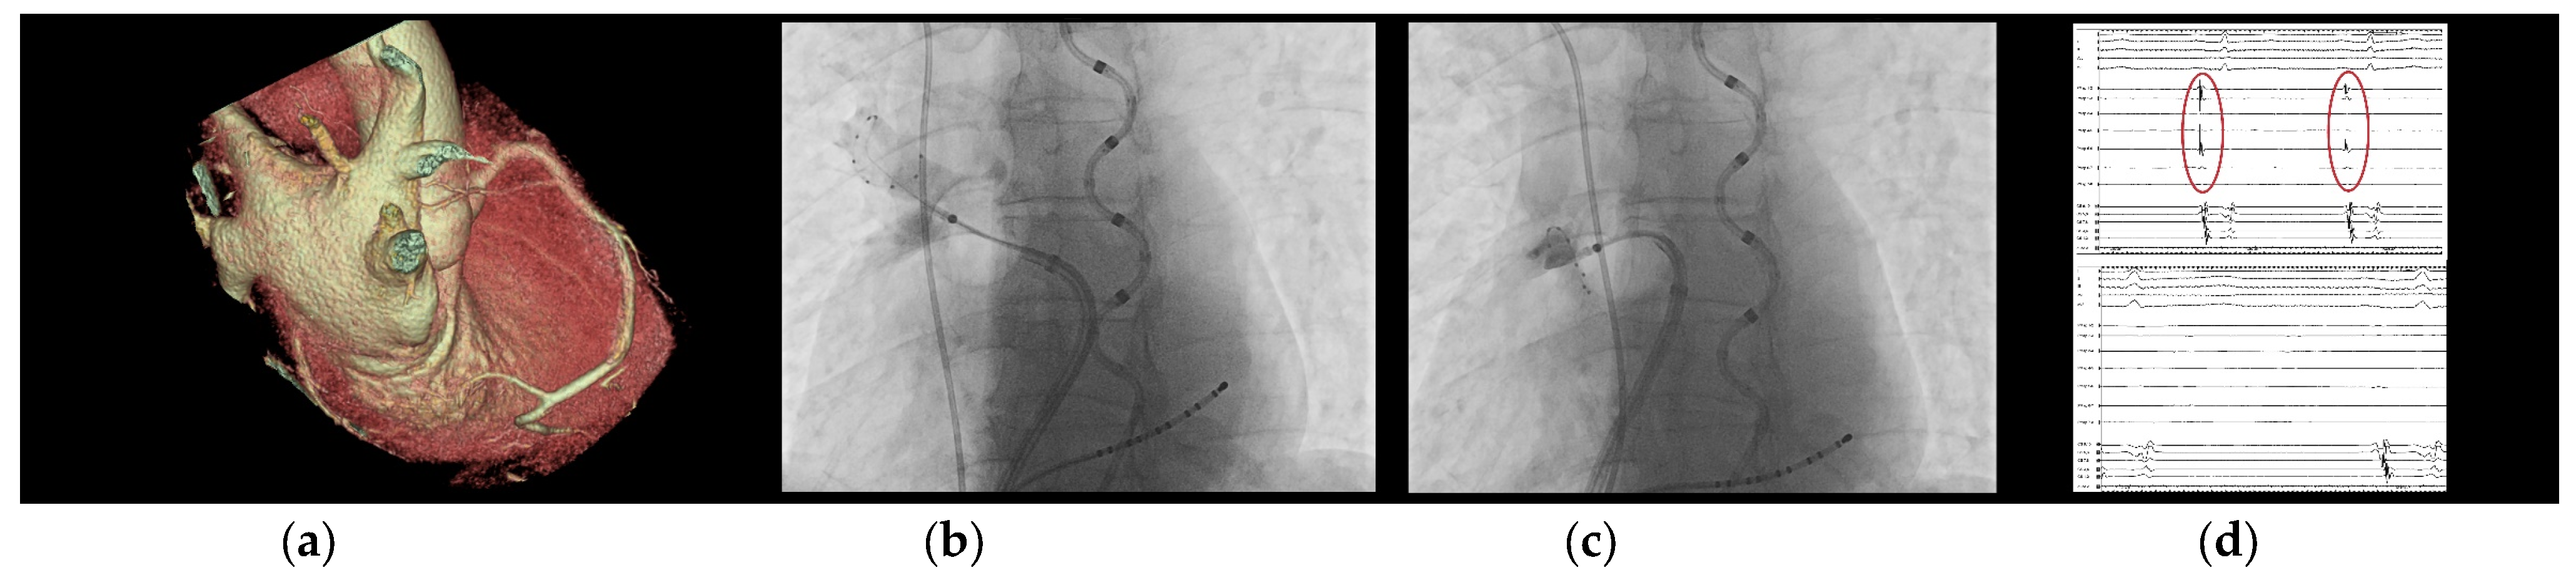

- In several clinical scenarios, the use of this new CB feature has helped the operator to reach an easier PVI, such as in cases with common PV trunks, accessory PVs, and funnel-shaped PV ostia.

4.2. Case-Based Approach